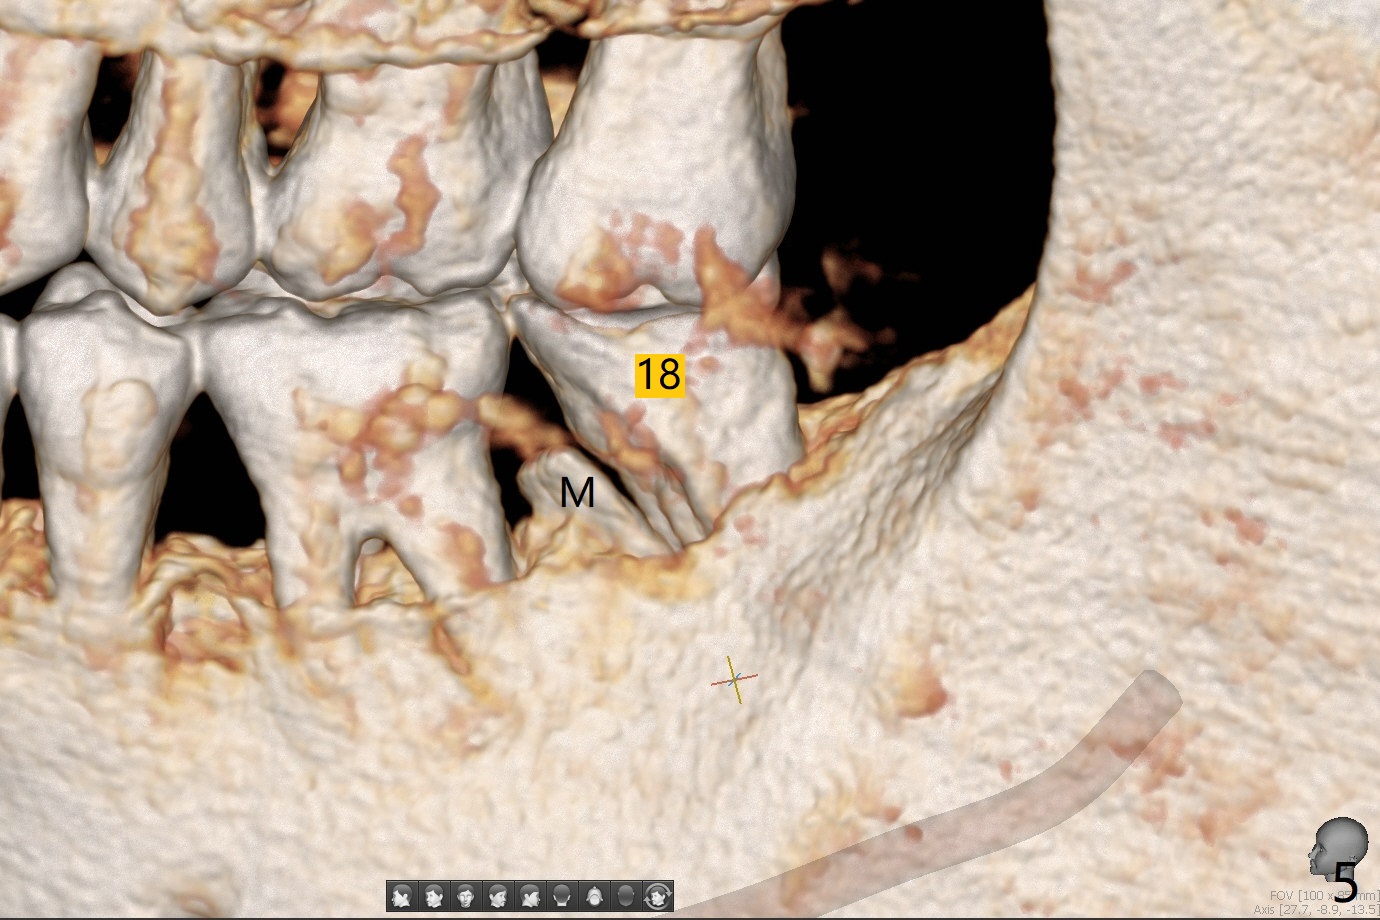

A 54-year-old man returns for #28 and 31 implants 3 months post extraction (#8,9 implants 4 years 5 months post cementation, Fig.1). The buccal plate at #28 is concave (Fig.2 *). After 2.2 mm drill to the depth as lingual as possible (Fig.3 L), use bone expanders through the guide to push the buccal plate out. Use Magic split or bone scalpels and blades to facilitate the expansion if needed. Place mixture of autogenous bone from #18 (Fig.4) and allograft buccally before implant insertion. Vertical fracture of the mesial root at #18 is an incidental finding (Fig.5 M). To avoid the impacted 3rd molar, osteotomy will be initiated as mesial as possible (Fig.6).